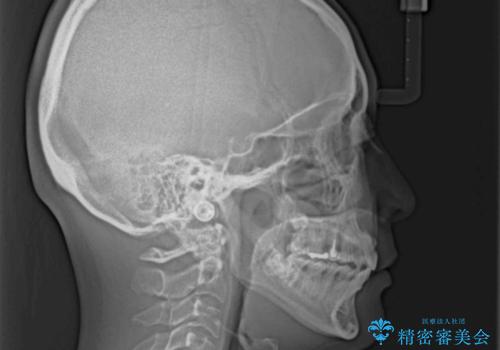

- 飛び出た上の前歯を気にして来院された患者様です。

奥歯の咬み合わせは、上顎歯列が理想的な一よりも数mm前方にある状態でした。

なるべく早めに治療を終えたいとのことで、補助装置を用いて上顎臼歯を後方に移動させ、同時にワイヤー装置にて整えることとしました。

舌の突出癖が原因で上下の歯に大きなスペースが生じていたため、舌のトレーニングをしっかり行っていただくことで、上顎歯列をスムーズに移動させることができました。